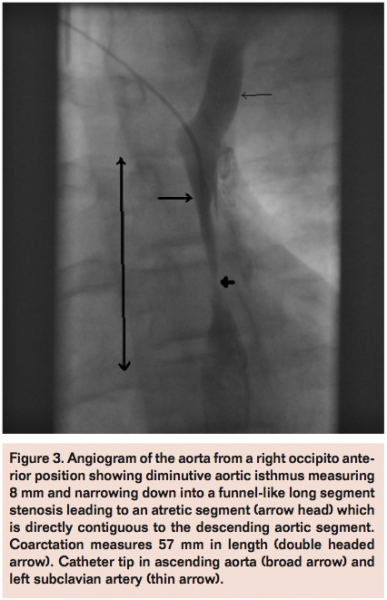

A 15-year-old boy was referred for assessment of severe systemic hypertension with a blood pressure of 180/110. He was unresponsive to medical therapy and renovascular causes of hypertension were excluded. Cardiac evaluation demonstrated a severe, atretic coarctation of the thoracic aorta. CT angiography demonstrated a left sided arch, with a well-developed 14 mm transverse aortic arch. There was normal branching of the head and neck vessels. The aortic isthmus was diminutive, measuring 8 mm and narrowing down into a funnel-like long-segment stenosis leading to an atretic segment, which was directly contiguous to the descending aortic segment (Figure 3). The proximal stenotic and “hypoplastic” segment spanned over 31 mm and 25 mm below the atretic segment. There were numerous collaterals communicating with the descending aortic segment. The femoral artery was cannulated and the atretic segment probed from below. It was not possible to cross; hence, right radial access was obtained with a 4 Fr sheath and this permitted passage of an 0.035-inch Terumo wire from the upper thoracic aorta to the descending segment below the atretic portion. The wire was snared using a 10 mm gooseneck snare and exteriorized through the femoral sheath. A 45 mm covered CP stent was then deployed over a 12 mm BIB balloon. The upper stenotic segment above the atretic portion was moderately resistant to inflation to 8 atm and only expanded to 9 mm whereas the lower half of the stent expanded appropriately to the 12 mm. However, the position was stable and there was no residual gradient across the stent. The procedure was uncomplicated.